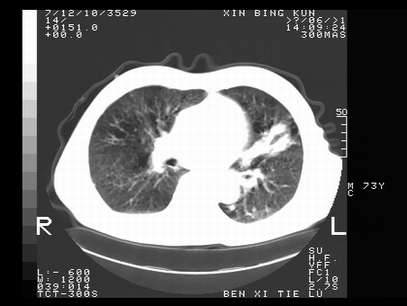

标题: CT10820:男,73岁,病史肺TB,现病史肺炎,直肠CA术后 [打印本页]

标题: CT10820:男,73岁,病史肺TB,现病史肺炎,直肠CA术后

双肺间质改变,依据病史双肺多发结节灶考虑转移,少量胸水.

1.两肺结核.2.两肺多发转移瘤.3右侧少量胸腔积液4.主动脉钙化.

双肺多发结节及条片状致密影,右侧少量胸腔积液。临床:直肠ca术后,肺tb病史。综合考虑:1 双肺转移!2 继发性肺结核合并感染!

此人病史较复杂,原有肺结核,直肠癌术后。肺部病灶形态亦呈多形性。因此,不可仅以一种病来解释肺部的病变。双肺多发的类圆形结节灶,结合病史还是首先考虑转移瘤,而双肺其余病灶还需结合化验室检查,结核或肺部感染在无其它检查资料的情况下不好排除。还是那句话----放射科医生不是开照像馆的,我们也是医生,看片一定要多结合临床及其它检查资料。要当一名合格的放射科医生,并不比当一名临床医生容易,我们可别把自已不当医生看。

两肺多发结节影,并见滋养动脉与其相连,考虑 两肺转移. 右侧胸腔积液考虑胸膜转移.

左肺上叶下叶背段,右肺中下叶见多发斑片状、条索状高密度影,兵变周围小结节影形成“树芽”样改变。 左肺上叶舌段近前胸壁处及右肺中叶内侧段见结节影。右侧胸膜腔内见液体密度区。纵隔内未见明确增大淋巴结。考虑左肺上叶舌段近前胸壁处及右肺中叶转移瘤可能性大。两肺继发型肺结核。右侧胸腔积液。